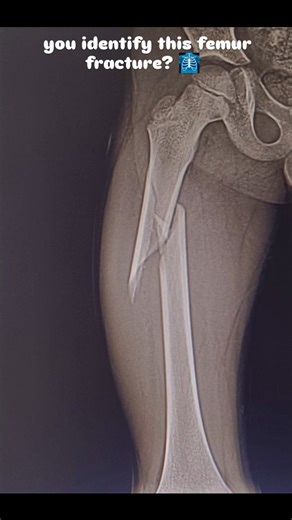

Views - Femur

Fracture - Broken

Child - Fractured